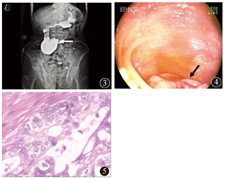

患者男,86岁,因恶心、呕吐伴消瘦半年余于2014年7月21日入院。入院前半年无明显诱因下出现间歇性恶心、呕吐,每5~6 d发作1次,每次持续1 d,呕吐物为胃内容物及黄绿色胆汁,呕吐后恢复正常,无腹痛、纳差,半年内体质量减轻15 kg。既往无高血压、糖尿病、心血管疾病史。入院体格检查:消瘦貌,皮肤巩膜无黄染,血压120/70 mmHg(1 mmHg=0.133 kPa),心率72次/min,律齐,两肺呼吸音粗,未及啰音,腹平软,无压痛,肝脾肋下未及,双下肢无水肿。2014年5月25日外院上腹部增强CT示:十二指肠远端近空肠处肠壁局部增厚伴周围淋巴结增大,考虑肿瘤可能大,十二指肠水平段局部受压,十二指肠淤积?2014年6月23日复查上腹部增强CT,提示肝脏多发小低密度灶,肝门部胆管扩张,胰腺萎缩(图1)。小肠CT未见明显异常(图2)。胃镜示浅表性胃炎。

入院后完善各项实验室检查。血常规:Hb 100 g/L,余正常;尿、粪常规、凝血功能正常。肝功能:总胆汁酸13.8 μmol/L,总蛋白53 g/L,白蛋白32 g/L,球蛋白21 g/L,前白蛋白215 mg/L,碱性磷酸酶45 U/L,γ–谷氨酰转酞酶20 U/L,葡萄糖4.9 mmol/L。肾功能:尿素7.9 mmol/L,肌酐71 μmol/L,尿酸78 μmol/L。电解质:钾、钠、氯化物、钙、磷、镁、铁均正常。血脂:总胆固醇2.52 mmol/L,三酰甘油0.32 mmol/L,高密度脂蛋白0.87 mmol/L,低密度脂蛋白1.47 mmol/L。血清肝炎标志物:抗–HBs 35.64 U/L,余均阴性。肿瘤标志物:AFP、CEA、CA19–9、糖类抗原50、糖类抗原72–4均正常。腹部X线平片(立卧位)未见明显异常。超声检查:肝右叶高回声结节,考虑血管瘤可能,肝质不均,胆囊胆固醇结晶,胰体、脾未见明显异常,门静脉系统、肝静脉系统、脾静脉系统彩色多普勒超声参数未见明显异常,中上腹腹主动脉旁未见明显异常肿大淋巴结。十二指肠低张钡剂造影:胃、十二指肠及部分小肠内见造影剂影;十二指肠降部扩张,造影剂潴留。钡剂通过十二指肠水平部缓慢,十二指肠于空肠交界处黏膜紊乱,1 h后腹部X线平片检查示十二指肠降部扩张,造影剂潴留,考虑十二指肠水平部肠腔狭窄(图3)。经口小肠镜(图4):十二指肠水平部占位(增殖性病灶,绕肠一周,肠腔狭窄)。遂转至外科进行手术治疗,术中见十二指肠、横结肠肝曲与胆囊粘连,肿瘤位于距屈氏韧带约4 cm处,侵及肠腔一周,累及浆膜外。切除标本示病灶为溃疡型肿块,大小为5.0 cm×1.5 cm×0.5 cm,切面灰白、质硬,累及肠管一周,浸润管壁全层。肠系膜少量脂肪组织中找到结节样组织2枚,最大径为0.5~1.2 cm。组织病理学诊断:腺癌Ⅱ~Ⅲ级,浸润至浆膜外,侵犯神经;肠系膜结节样组织中1枚为淋巴结,见癌转移,另1枚为癌结节(图5)。术后诊断为十二指肠腺癌。术后2周出院,出院后随访2个月,患者进食可,无腹胀等不适。